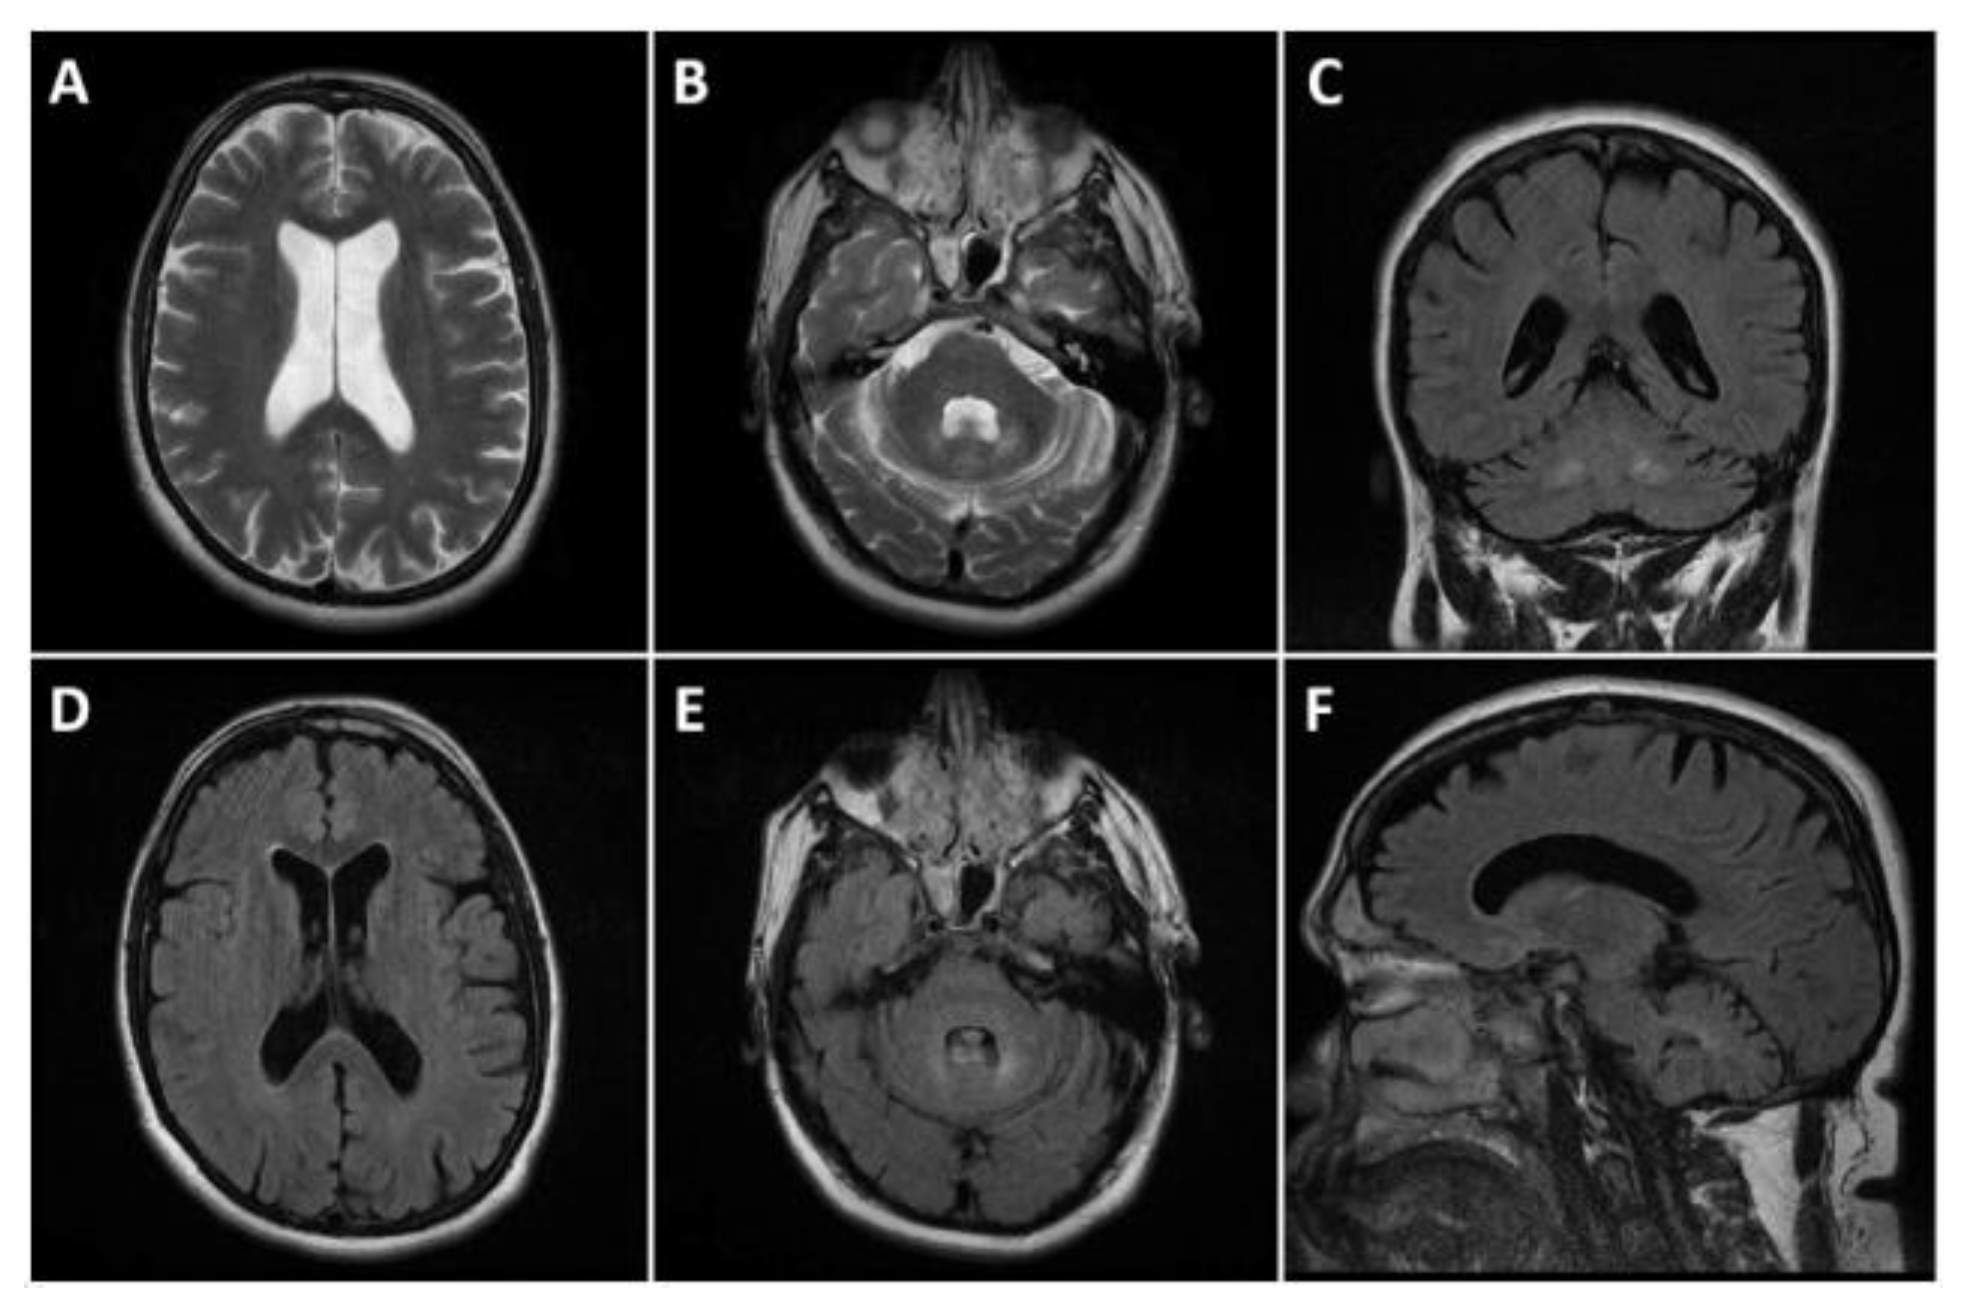

The magnetic resonance imaging (MRI) of the head showed dilatation of the cerebral ventricles, cortical atrophy, and bilateral changes in the signal intensity in the zones of the nuclei dentati (increased signal of T2 and T2 FLAIR images, without significant changes in diffusion and gradient images). The ventricular system, cerebral cistern, and subarachnoid fluid spaces on convex were dilated (Figure 2). The electroencephalogram (EEG) showed diffuse medium-voltage, and in places high-voltage, bisynchronous theta activity with single spike–wave discharges (SWDs). The T carotid artery duplex scan was normal.

Figure 2.

Head MRI presenting cortical atrophy and bilateral changes in the signal intensity in the zones of the dentate nucleus. (A,B): T2 axials; (D,E): FLAIR axials; (C): FLAIR coronal, and (F): FLAIR sagittal. Dilated ventricular system and subarachnoid fluid spaces on the convexity bilaterally (A,D). Symmetric T2 and FLAIR hyperintensities affecting the dentate nuclei (B,C,E,F).

Neuroimaging findings in CTX are also variable. The most common MRI abnormalities include T2/FLAIR hyperintensity in the cerebellar dentate nuclei and corticospinal tracts, as well as spinal cord atrophy [14]. This was also present in our case. However, the severity of MRI changes does not consistently correlate with the degree of cognitive impairment [15]. Electroencephalogram (EEG) findings, such as diffuse slow waves, have also been reported in CTX patients [16].